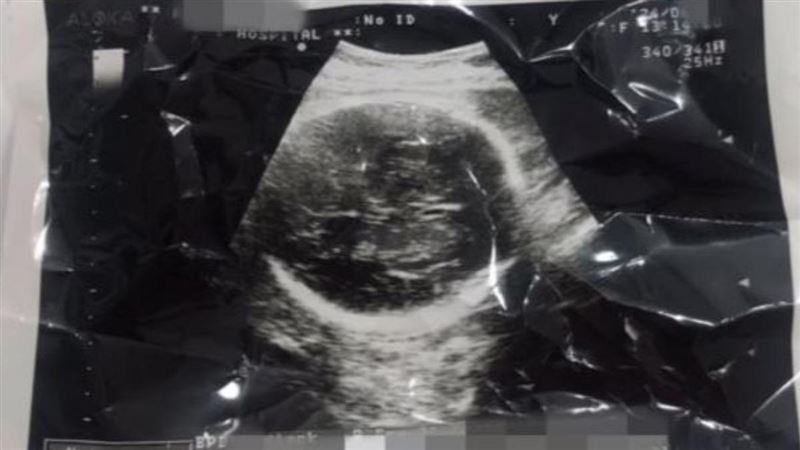

▲南韓壹名女子自稱懷孕36周墮胎,還將墮胎過程拍成紀錄片,遭控「謀殺胎兒」。(圖/翻攝當事人Youtube)

綜合外媒報導,這名自稱懷孕36周的女子,在6月27日把自己墮胎的影片上傳至網路,她在影片中宣稱,她不知道自己懷孕,直到去醫院檢查才知道胎兒已滿36周,並分享當時胎兒的超音波影像,當時胎兒幾乎已發育完全。